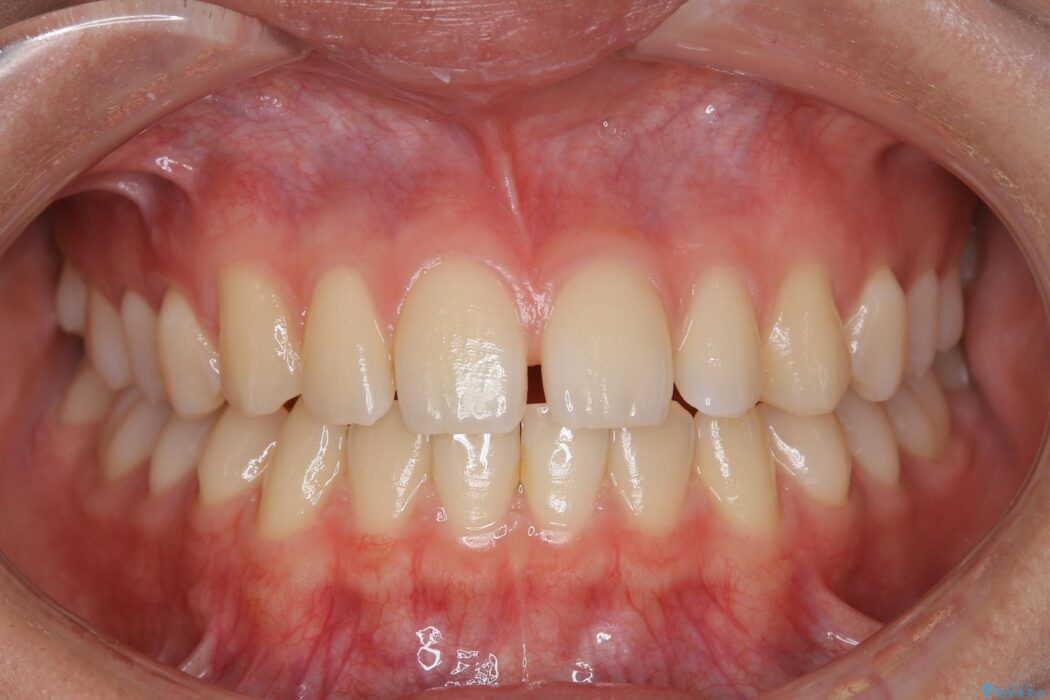

すきっ歯を改善したいとご来院された患者様です。

インビザライン・クリンチェック(シミュレーション)を行い、インビザラインライトで治せる範囲であると診断し、矯正治療を行いました。

マウスピース14枚・期間4ヶ月で主訴であるすきっ歯を改善し、治療を終えることが出来ました。